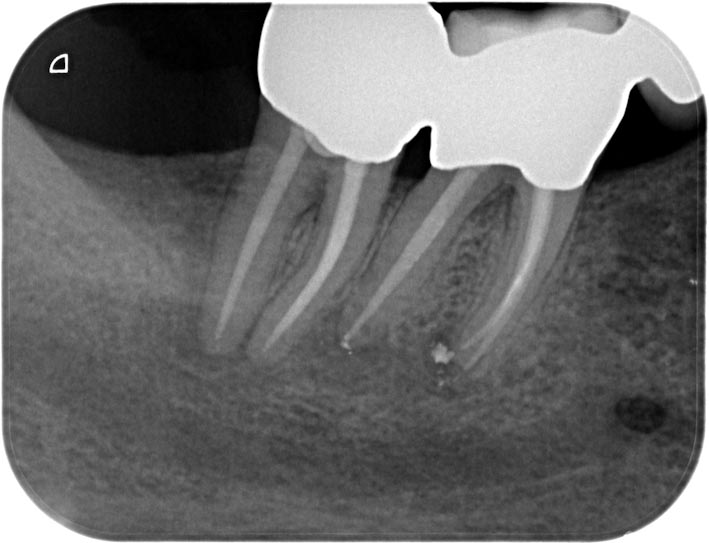

4746-2 Veröffentlicht 4. Juni 2013 am 709 × 543 in Recall Zähne 47 46 mit apikalen Aufhellungen Rö 47 46 Recall 6 Monate post WF